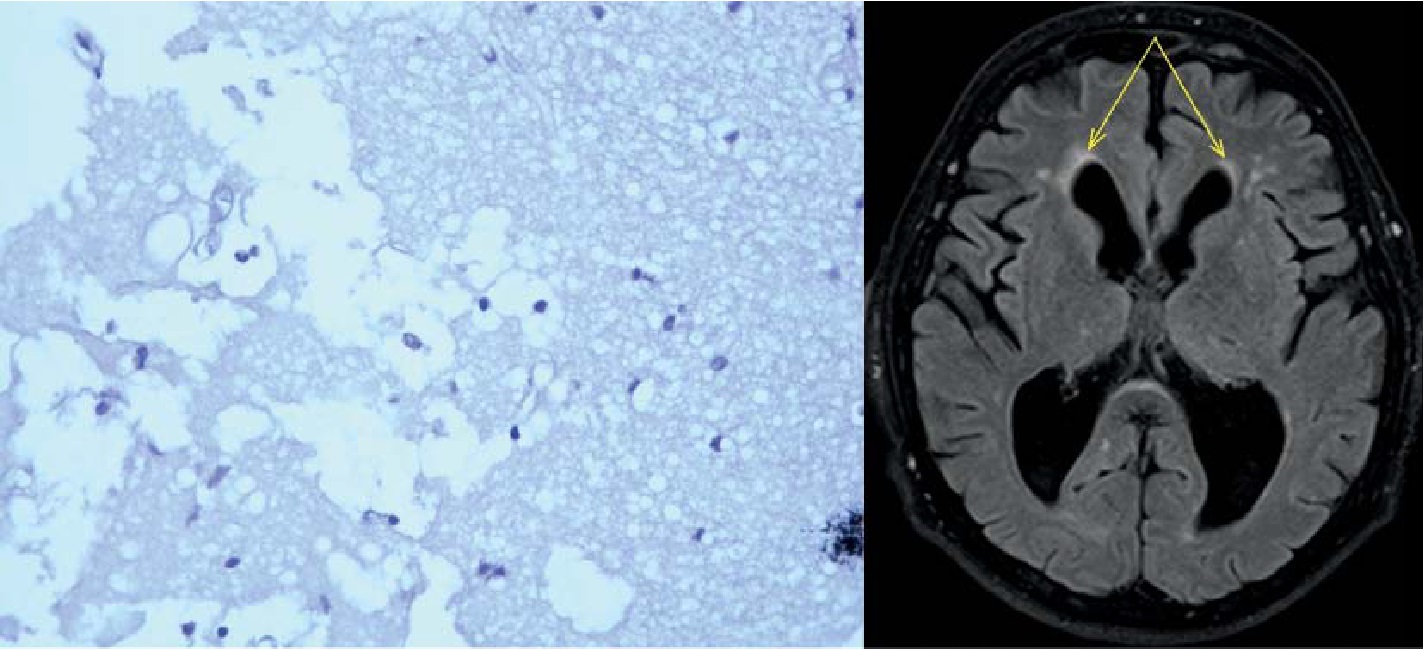

Наиболее выраженные изменения в веществе головного мозга у пациентов, страдающих ИНТГ, были связаны с общим разрежением нейропиля, утолщением и склерозированием стенок артериол, набуханием эндотелия, образованием конвалютов. Периваскулярные пространства часто были расширены, иногда значительно, с образованием криблюр (рис. 1).

Рис. 1. Кора. Крупная криблюра, в просвете небольшое количество рыхло расположенных коллагеновых волокон и свободно лежащие макрофаги и лимфоциты. Окраска гематоксилином и эозином, ув. ×400